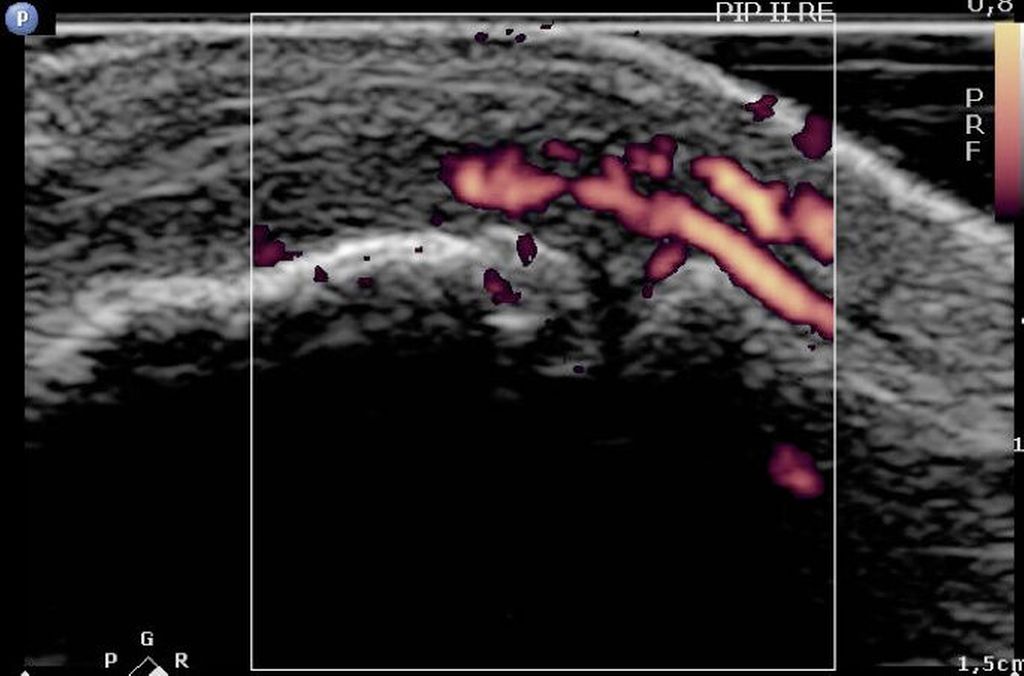

Abb. 4: Sonografie des PIP II bei Erstvorstellung einer Patientin mit akuten Beschwerden in den Fingergelenken. Es zeigt sich eine deutliche synoviale Hyperämie in der Power-Doppler-Sonografie als Ausdruck einer Synovitis bei noch negativem Röntgenbefund. Man beachte die hohe räumliche Auflösung dieser Bildgebung!

Die Sonografie bietet unter Verwendung spezieller hochfrequenter Schallköpfe eine ausgezeichnete räumliche Auflösung. Ein weiterer Vorteil ist die Möglichkeit der Darstellung der Perfusion mittels Doppler-Sonografie, was auf einfache Weise eine funktionelle Information erbringt. Dadurch eignet sich die Sonografie ganz speziell für die Untersuchung rheumatoider Veränderungen der kleinen Gelenke, klassischerweise der Fingergelenke (Abb. 4). Durch den geringen gerätetechnischen Aufwand kann die Untersuchung direkt im Rahmen der klinischen Untersuchung erfolgen, was eine erhebliche Vereinfachung und Verkürzung des diagnostischen Weges mit sich bringt. Die Eindringtiefe und das sinnvoll untersuchbare Volumen sind jedoch deutlich begrenzt. Auch schränkt eine Überlagerung durch knöcherne Strukturen die Bildgebung ein.